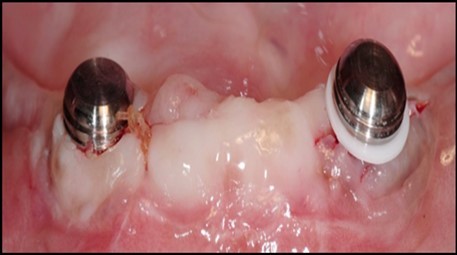

Post operatively after 3 months, osseointegration was evaluated clinically and radiographically (Figure 5a,b) and the implants were well prepared to receive the prosthesis. The second stage surgery was performed in which cover screws were removed and healing abutment were inserted into the implants (Figure 6). After a time period of two weeks, peri-implant soft tissue healing was examined, and existing denture was relined after relieving at the abutment site. Later, the healing abutment is removed using a 1.25 mm hex driver. Internal portion of the implant is irrigated and dried to make sure if it is free of debris and soft tissue. A periodontal probe was used to measure the gingival cuff height at the right and left canine site of implant location. Selected ball abutment were placed onto each implant using 1.25 mm hex driver and 30 Ncm torque wrench (Figure 7A).

Figure 7.(A) View of 2.0mm and 5.0mm post Locator Abutments with a 2.0mm post. (B) Placement of the Locator Abutment after the well of implant has been cleaned with alcohol on a cotton-tipped applicator.